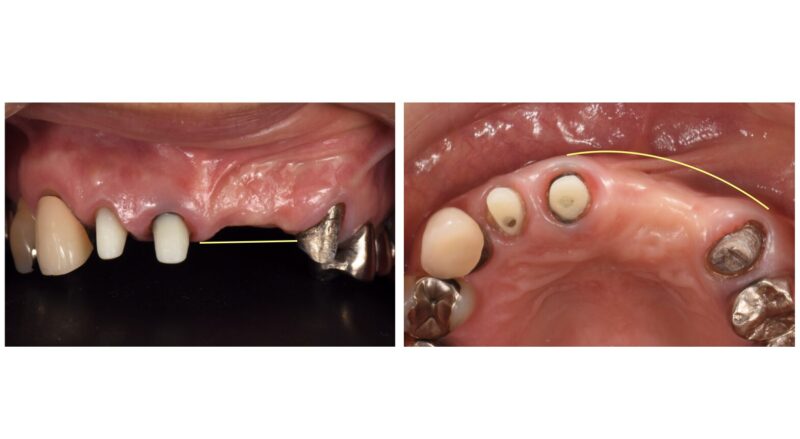

今回掲載の患者は初診時に入っていた仮の歯はタテにもヨコにも歪んでおり、左上の歯はすでに2本失っている状態でした。(資料1)

一般的に歯を抜いた後、そのまま放置すると骨や歯肉は時間とともに痩せてしまいます。(資料2〜5)